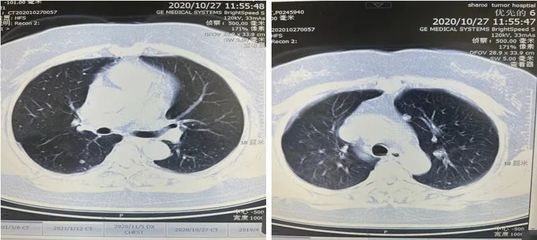

另外,生气的人更容易导致免疫功能低下,免疫功能受损,容易引起肺结节。那么中医如何解决这种“气怒”的肺结节人群呢?分享几个案例。案例1:马先生,65岁,吸烟30多年。2020年7月,因胸闷、胸痛、憋气等症状到医院就诊。CT检查后显示双肺多发结节。左肺下叶胸膜下有较大的实性结节,直径约6 mm,未给予其他治疗。